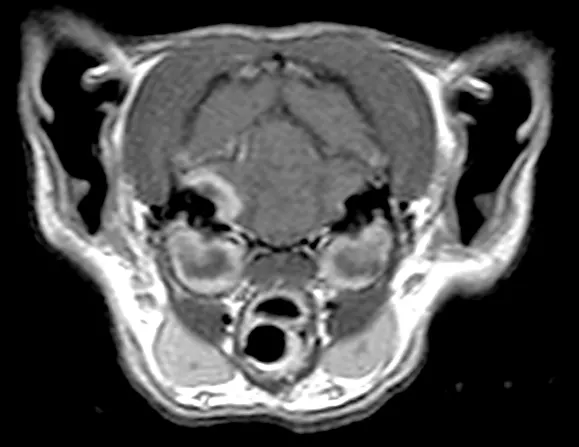

Figure 2

MRI showing postcontrast enhancement of a bacterial abscess and meningitis. There is also evidence of a fracture in the bone immediately adjacent to the abscess.